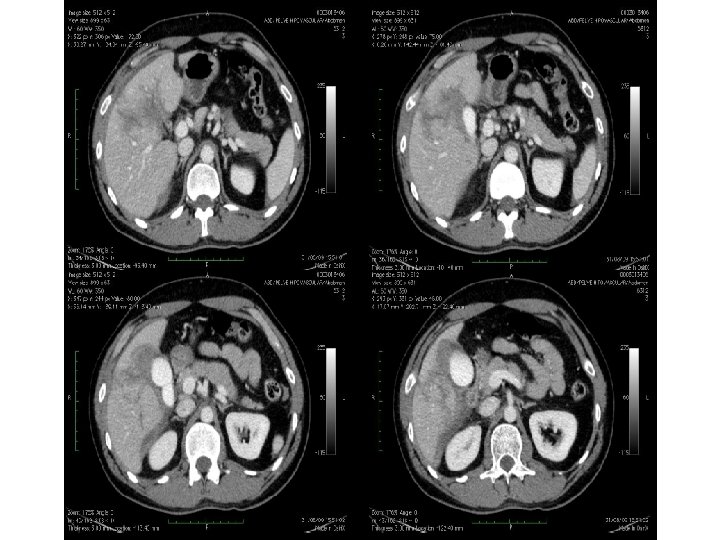

Trauma hepático Melhor exame: TC - S = 100% - E = 94% • Pista diagnóstica: evidência de lesão parenquimatosa irregular associada a hemorragia intra e perihepática • Lobo direito: 75% • 2ª víscera mais afetada no trauma * Maioria dos hematomas subcapsulares são iatrogênicos pós-biópsias • Suspeitar: dor, sensibilidade, rebote +, defesa, hipotensão, hematêmese/melena (hemobilia), icterícia. Lab: de Br e FA

Trauma hepático – achados na TC • Lacerações: – Simples: lesão hipodensa linear solitária; – “Estrelada”: lesões hipodensas lineares ramificadas (paralela aos ramos da veia porta ou hepática) – Superficial: < 3 cm; profunda: > 3 cm • Hematoma: parenquimatoso x sucapsular (formato lenticular) – Não coagulado (menos tempo): hiperdenso em relação ao parênquima hepático não contrastado e hipodenso em relação ao contrastado – Coagulado: mais denso que o não coagulado

Hemorragia ativa: área focal de atenuação de contraste em fase arterial. Se persistir: falha no tratamento conservador

Caso clínico • - JCC, sexo masculino. • - Vítima de acidente automobilístico • - Dor Abdominal

• Conduta clínica: Optado por tratamento conservador das lesões hepáticas, com acompanhamento clínico e controle de hematócrito. • 06 dias após o trauma: • Paciente evolui estável, porém apresentando pico febris. • Solicitado exame para controle das lesões hepáticas e pesquisa de coleções